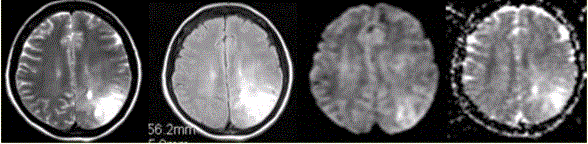

女性,42岁。癫痫1个月,近期加重。无发热,无其他病史。MRI表现如下图。为进一步确诊,MRI增强检查及MRS(Cho升高)结果如下图。可能的诊断...

问题 女性,42岁。癫痫1个月,近期加重。无发热,无其他病史。MRI表现如下图。 为进一步确诊,MRI增强检查及MRS(Cho升高)结果如下图。可能的诊断为

选项 A.脑脓肿 B.转移瘤 C.星形细胞瘤 D.结核瘤 E.脑膜炎

答案 C